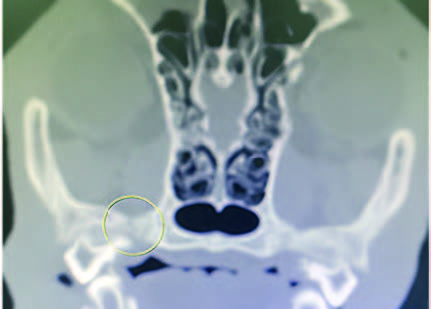

CT scan of skull is preferred for evaluate bone fractures and identify areas of acute hemorrhage or edema. CT scan showed multiple sites of skull fractures, right maxilla, both frontal, right zygomatic, right caudal mandible, right caudal zygomatic, right temporal, left occipital bone (Figure 3) and patchy small area of hyper-attenuation at the cranial of midbrain in pre-contrast study (Figure 4), no detectable mass effect, hypo-attenuated of large edematous parenchyma in the brain, right temporomandibular joint is displacement (Figure 5) and left tympanic bulla shows partial ventral fluid-filled.

Figures 3.1, 3.2, 3.3, 3.4, 3.5, 3.6, 3.7

Figures show multiple sites of skull fractures, right maxilla, both frontal, right zygomatic, right caudal mandible, right caudal zygomatic, right temporal, left occipital bone.